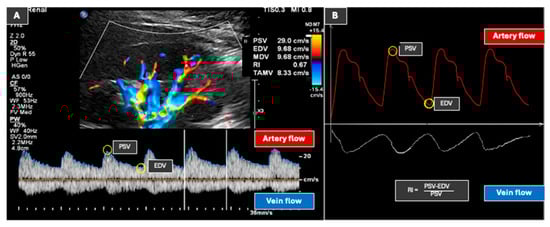

Duplex-Doppler ultrasonography has become an essential tool in the diagnosis and management of kidney diseases, allowing clinicians to assess renal hemodynamics, detect vascular abnormalities, and monitor disease progression. Among the various Doppler-derived parameters, the renal resistive index (RRI) has gained particular attention both [...] Read more.

Duplex-Doppler ultrasonography has become an essential tool in the diagnosis and management of kidney diseases, allowing clinicians to assess renal hemodynamics, detect vascular abnormalities, and monitor disease progression. Among the various Doppler-derived parameters, the renal resistive index (RRI) has gained particular attention both as a diagnostic tool and a prognostic marker in nephrology. Traditionally considered an indicator of parenchymal perfusion, recent evidence highlights its strong association with systemic hemodynamic factors, particularly arterial stiffness, positioning RRI as a valuable tool for evaluating patients with systemic vascular impairment, such as hypertension, diabetes mellitus, and atherosclerosis. RRI has been strongly linked to vascular damage, which in turn is influenced by inflammation and endothelial dysfunction, making it a reliable marker of cardiovascular damage and a potential predictor of cardiovascular risk. Furthermore, emerging studies suggest that RRI could serve as a dynamic parameter to monitor vascular changes induced by therapeutic interventions. This narrative review summarizes the classic and evolving applications of RRI, from its origin as a renal hemodynamic marker to its emerging role as a systemic vascular biomarker with diagnostic and prognostic significance in cardiovascular and metabolic diseases. Full article

Background: Diabetic kidney disease (DKD) is a significant risk factor for End-Stage Renal Disease, with a high global incidence and mortality rate. Hyperglycemia in DKD induces inflammation, contributing to glomerular hyperfiltration, fibrosis, and impaired renal function. Current therapies, including SGLT2 inhibitors, ACE inhibitors, and ARBs, show limited efficacy. Autologous dendritic cells (DCs) offer potential anti-inflammatory effects by reducing cytokine activity and fibrosis biomarkers. Methods: A quasi-experimental pretest–post-test design was conducted involving 29 DKD patients. Baseline blood and urine samples were collected for MMP-9, TGF-β, and Doppler ultrasound (PSV, EDV) measurements. The subjects received subcutaneous injections of autologous DCs, and follow-up measurements were conducted four weeks after treatment. The statistical analyses included paired t-tests, Wilcoxon signed-rank tests, and linear regression. Results: After treatment, there were a significant decrease in PSV (from 47.1 ± 23.87 cm/s to 27.85 ± 20.53 cm/s, p = 0.044) and a significant increase in EDV (from 13 ± 5.32 cm/s to 15.7 ± 12.55 cm/s, p = 0.039). A strong correlation was observed between the TGF-β and MMP-9 levels (p = 0.001). Linear regression analysis showed reduced MMP-9 influence on the TGF-β after treatment, suggesting potential fibrosis reduction. Gender and UACR subgroup analyses revealed significant PSV and EDV improvements in females and the microalbuminuria group. Conclusion: Autologous dendritic cell therapy significantly improved renal hemodynamics and showed potential to reduce fibrosis by modulating TGF-β and MMP-9 levels in DKD patients, warranting further investigation. Full article